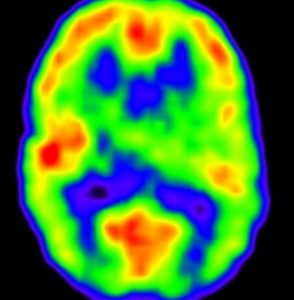

2歳6ヶ月,18グレイの全脳照射の影響

2001年,2歳1ヶ月で発症した退形成性上衣腫の男の子でした。腫瘍は第4脳室から左小脳橋角槽に伸展していましたが,全摘出しました。術後には小脳失調も無言症も脳神経麻痺もありませんでした。当時,退形成性上衣腫には脳脊髄照射が標準的治療でした。術後は何とかICE化学療法でつないで,2歳6ヶ月の時に,1日線量1.8グレイで,脳脊髄照射18グレイ,後頭窩23.4グレイ,腫瘍床12.6グレイ,腫瘍床総線量54グレイの放射線治療を行ないました。大脳と下垂体の被爆は18グレイ/10分割となります。

この画像は14歳の時のものです。大脳の萎縮は全くなく,小脳のダメージは最小限です。内分泌障害も無く甲状腺ホルモンも補充していませんが,背骨の伸びが悪いです。

5歳時 FIQ 79, VIQ 79, PIQ 85

14歳時 FIQ 75, VIQ 86, PIQ 68

神経心理学的検査からは,知能低下,記憶障害,注意障害があると診断されました。言語理解IQ 86,知覚統合IQ 71,注意記憶IQ 76,処理速度IQ 72です。全脳照射の18グレイばかりではなく,発症時の水頭症や小脳のダメージによる学習障害も加わっているのかもしれません。問題となってくるのは小学校高学年からですから,かなり長期的な観察が必要です。多くのお医者さんはせいぜい治療が終わってから自分では数年の観察しかしないので,治療を担当する先生がこのようなことを知らない可能性があります。